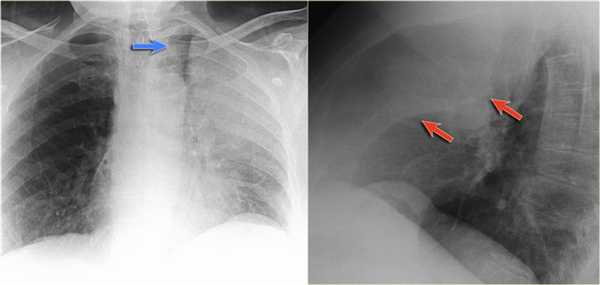

Но случаются ситуации, когда мы не видим никаких изменений, как на обзорной рентгенограмме в данном случае: практически легочные ткани. Но, посмотрите - корень левого легкого располагается на одном уровне с корнем правого легкого. Это позволяет нам предположить, нет ли тут какого-то процесса, который приводит к уменьшению объема.

На боковой рентгенограмме мы видим ателектаз язычковых сегментов, который в данном случае скрыт за тенью сердца. Именно этот процесс и вызывает смещение корня легкого.

Также очень частым проявлением ателектаза является подъем диафрагмы, что хорошо визуализируется на ниже представленной рентгенограмме (указано синий стрелкой).

У данного пациента карцинома легкого с билатеральным метастазированием в легкие (указано красными стрелкам).